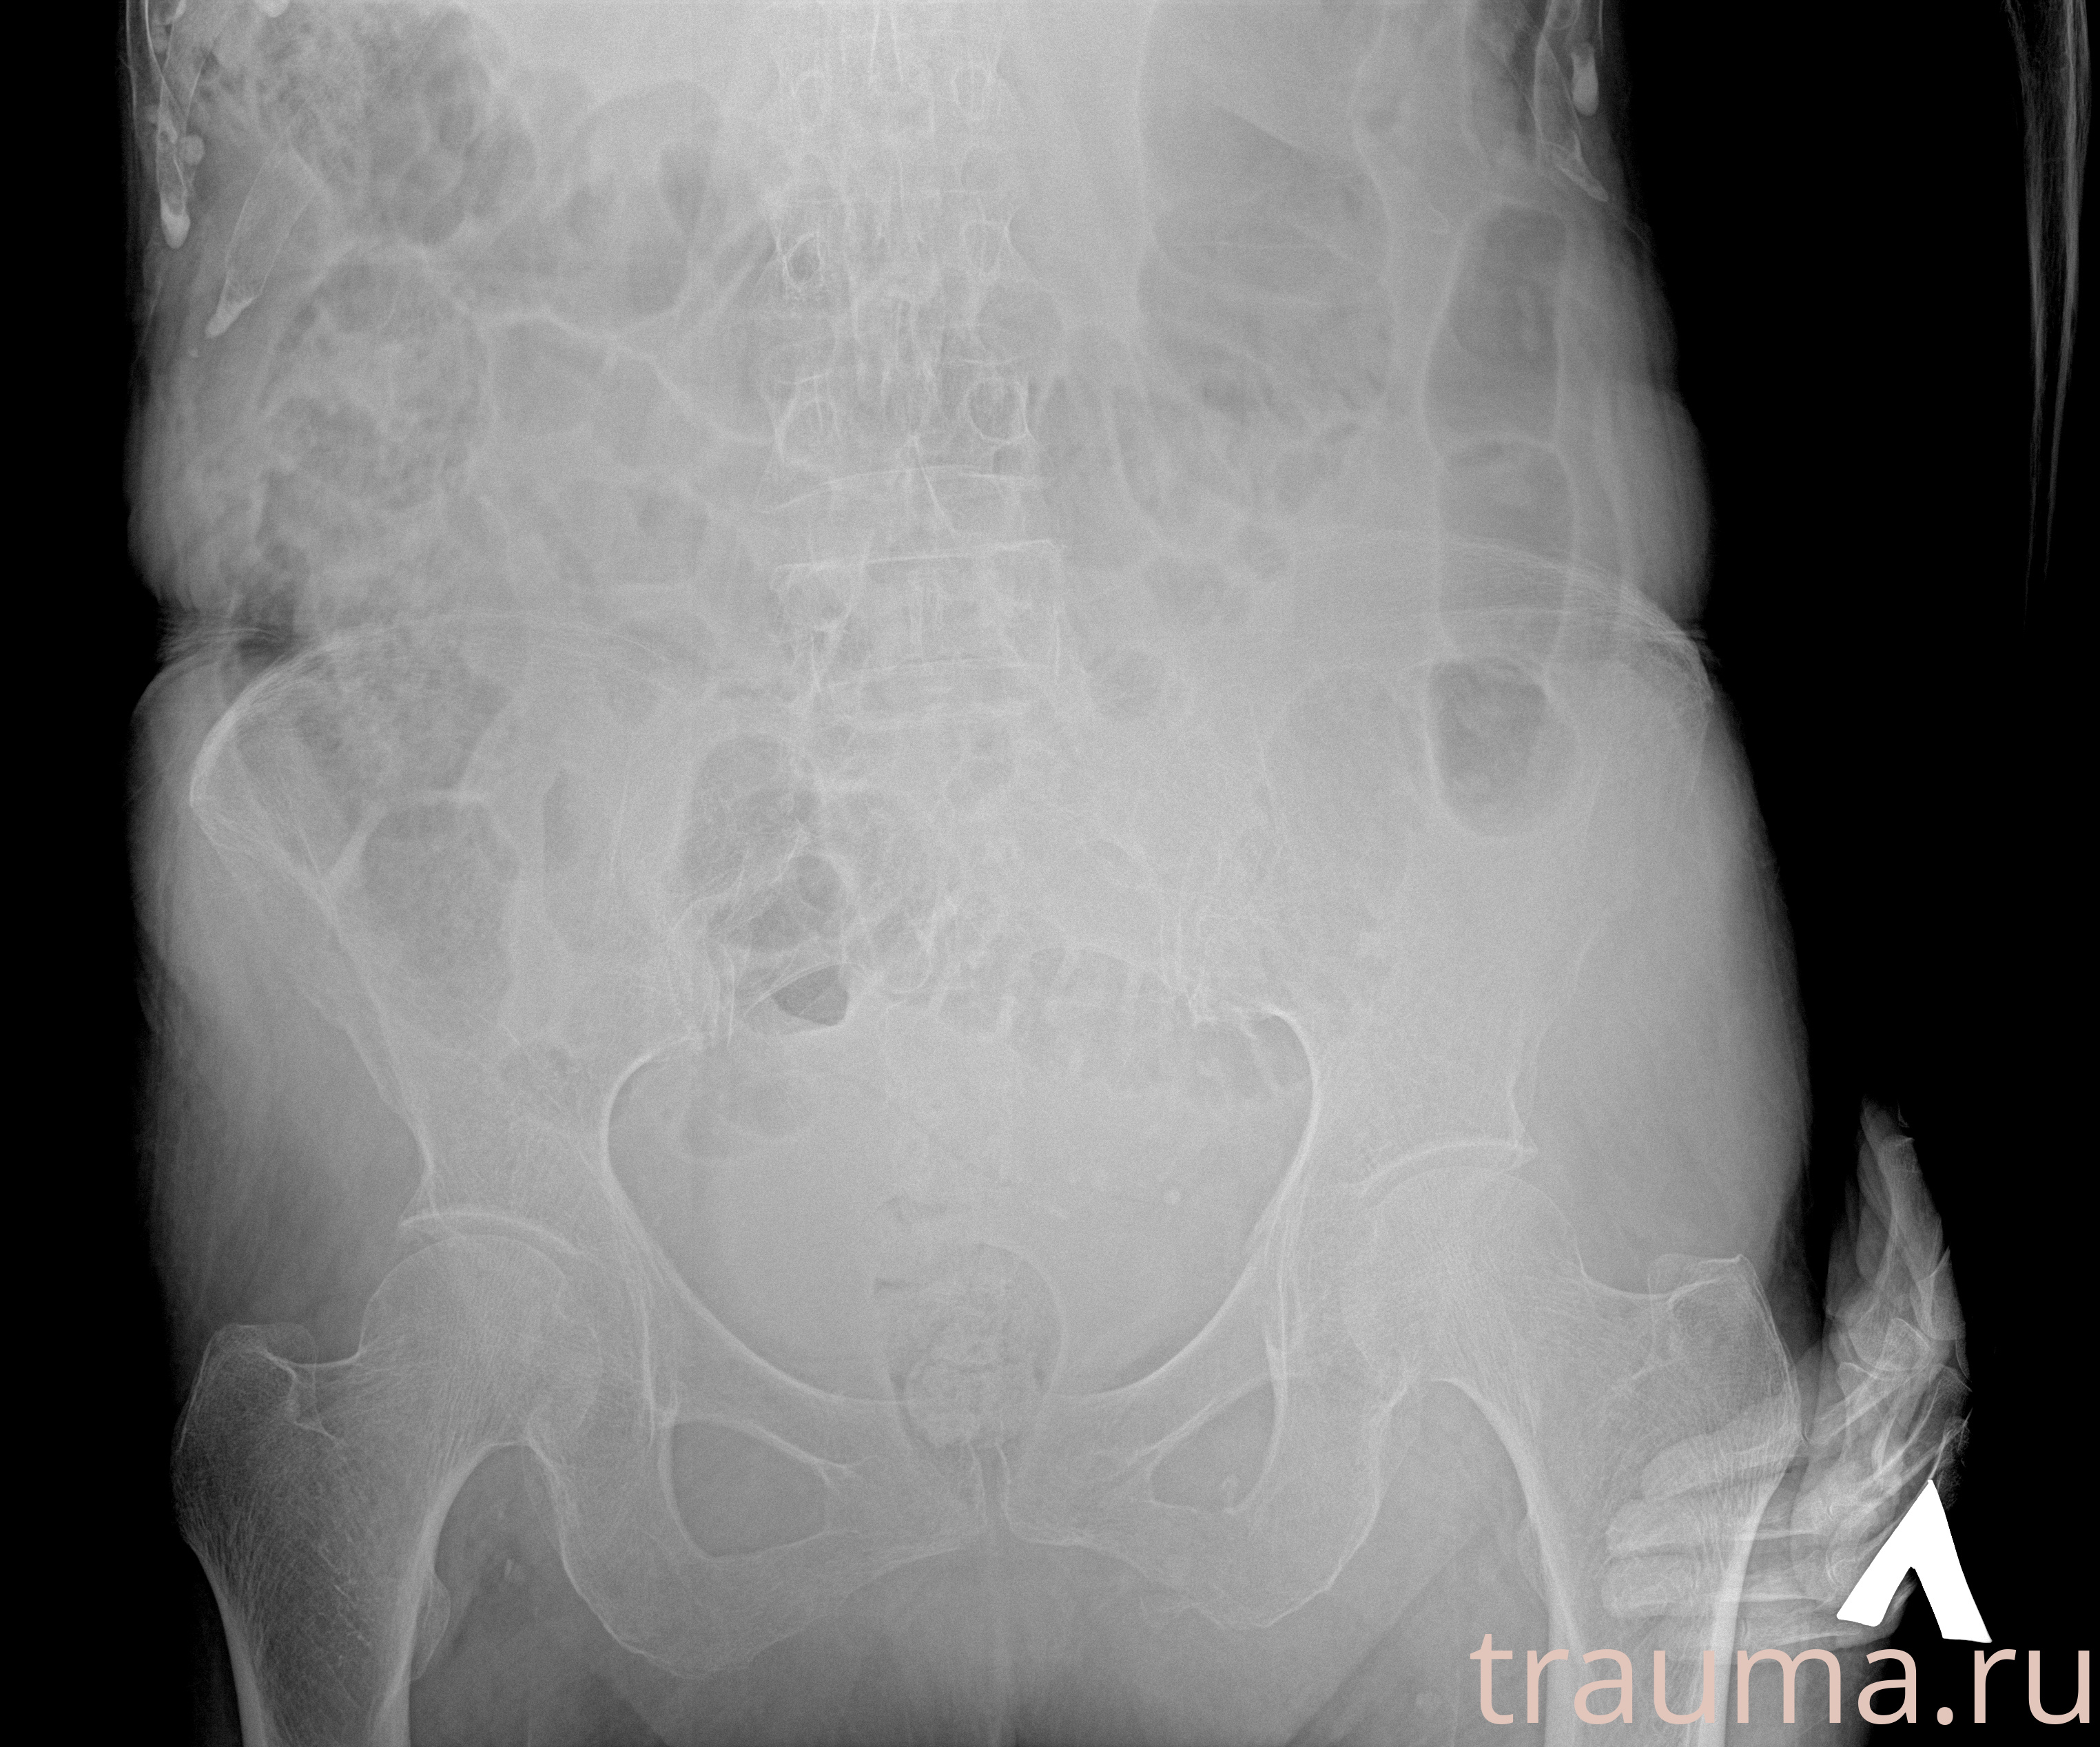

Рентгенограммы

Рентген на дому: по вашему адресу приезжает врач-рентгенолог, травматолог-ортопед с мобильным рентгеновским аппаратом, проводит диагностику травмы или заболевания, делает необходимые рентгенограммы, дает рекомендации по дальнейшему лечению. Получить качественные снимки в домашних условиях возможно благодаря уникальной методике, разработанной МосРентген Центром для института  Склифосовского